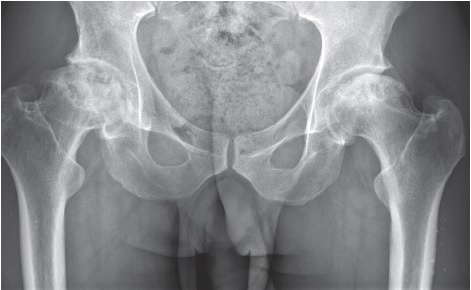

Upon admission, there were no visual signs of swelling or redness of the skin in the area of the hip joints. On palpation, there was local and axial tenderness in the projection of the right femoral head. The range of motion in the right hip joint was limited — external abduction 10°. Pain on the VAS was 5-6 points. The left hip joint was painless, with a full range of motion. There was a shortening of the right lower extremity by 2.0 cm. X-rays and CT scans showed signs of bilateral aseptic necrosis of the femoral heads, more pronounced on the right — stage 3B-4 according to ARCO (Fig. 4, 5). In blood tests, the ESR was accelerated to 58 mm/hr., other results were within reference values.

Fig. 5. Clinical case 2. X-ray in frontal projection — bilateral aseptic osteonecrosis of the femoral heads: right — stage 3B (late) according to ARCO